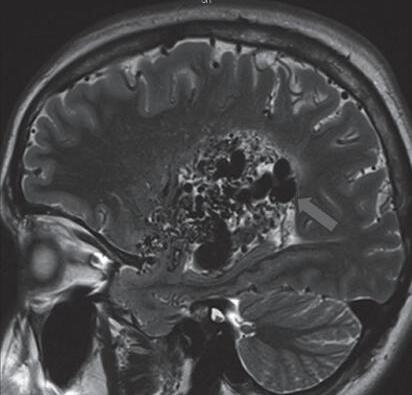

Fig. 1-16. RNM encéfalo T1 com contraste: (a) Coronal e (b) axial demonstrando MAV grau 4 frontoparietal esquerda. (c,d) Arteriografia cerebral AP mostrando a irrigação pelos ramos da cerebral anterior e média esquerda, além da cerebral anterior direita, com drenagem superficial para o seio sagital superior. Seta azul apontando para o nidus da MAV.

Fig. 1-17. RNM encéfalo T1 com contraste (a) axial e (b) T2 sagital demonstrando MAV grau 5 profunda temporoinsular esquerda com extensão nos núcleos da base. (c,d) Arteriografia cerebral,demonstrando a drenagem venosa profunda para veia cerebral interna (seta azul) com sinais de hipertensão.